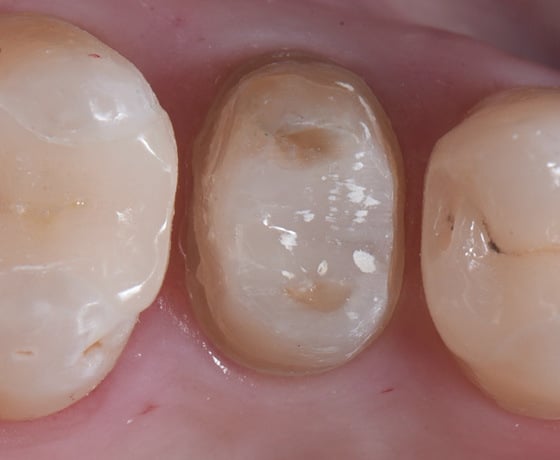

Pretrattamento con HF, risciacquo con acqua, adesivo 3M™ Scotchbond™ Universal Plus e cemento composito 3M™ RelyX™ Universal.

Restauri parziali dei molari e dei premolari superiori aderenti.